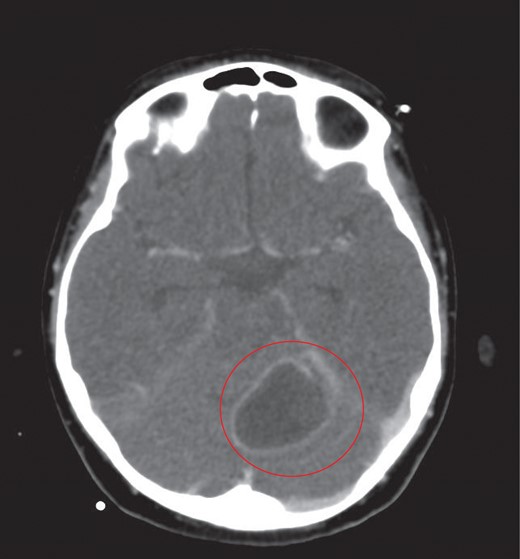

CT of the head with contrast revealed opacification of the left mastoid air cells with multiple ring enhancing abscesses throughout the brain, the largest of which in the left cerebellar hemisphere, measuring 4.4 × 2.9 cm in maximal axial dimensions (Fig. 6). There was non occlusive thrombus of the left internal jugular vein and superior sagittal sinus (Fig. 7). A repeat CT thorax revealed persisting left lung abscesses, a left sided collection and a new post drainage large, right-sided haemothorax.

The largest ring enhancing lesion was within the left cerebellar hemisphere. This was drained surgically.

CT scan of head with contrast revealed multiple ring enhancing lesions within the brain, opacification of the left mastoid air cells and thrombus within the superior sagittal sinus and left internal jugular vein.